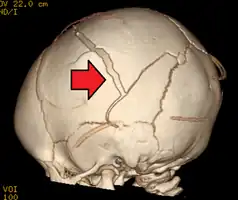

An intraparenchymal bleed with overlying skull fracture from abusive head trauma

Characteristic injuries associated with AHT include retinal bleeds, multiple fractures of the long bones, and subdural hematomas (bleeding in the brain).[5] These signs have evolved through the years as the accepted and recognized signs of child abuse. Medical professionals strongly suspect shaking as the cause of injuries when a young child presents with retinal bleed, fractures, soft tissue injuries or subdural hematoma, that cannot be explained by accidental trauma or other medical conditions.[6]

Fractures of the vertebrae, long bones, and ribs may also be associated with AHT.[8] Dr. John Caffey reported in 1972 that metaphyseal avulsions (small fragments of bone torn off where the periosteum covering the bone and the cortical bone are tightly bound together) and "bones on both the proximal and distal sides of a single joint are affected, especially at the knee".[9]

AHT may be misdiagnosed, underdiagnosed, and overdiagnosed,[26] and caregivers may lie or be unaware of the mechanism of injury.[11] Commonly, there are no externally visible signs of the condition.[11] Examination by an experienced ophthalmologist is often critical in diagnosing shaken baby syndrome, as particular forms of ocular bleeding are quite characteristic.[27] Magnetic resonance imaging may also depict retinal bleeding;[28] this may occasionally be useful if an ophthalmologist examination is delayed or unavailable. Conditions that are often excluded by clinicians include hydrocephalus, sudden infant death syndrome (SIDS), seizure disorders, and infectious or congenital diseases like meningitis and metabolic disorders.[29][30] CT scanning and magnetic resonance imaging are used to diagnose the condition.[11] Conditions that may accompany AHT include bone fractures, injury to the cervical spine (in the neck), retinal bleeding, cerebral bleed or atrophy, hydrocephalus, and papilledema (swelling of the optic disc).[12]